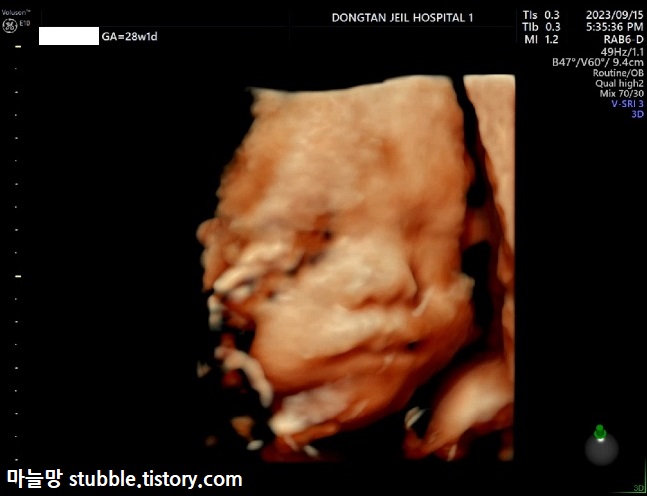

초음파선생님께서 이 사진을 뽑아주신 것을 보니 이 사진이 두 번째로 잘 나온 사진일 거예요.